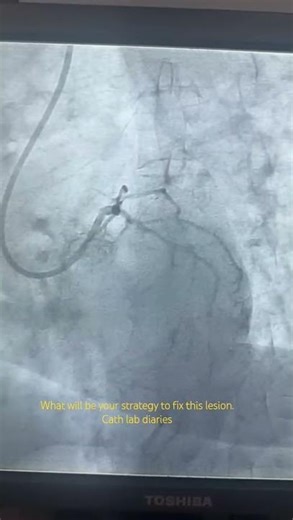

Interventional Cardiology NSTEMI 的热门建议 |

- Interventional Cardiology